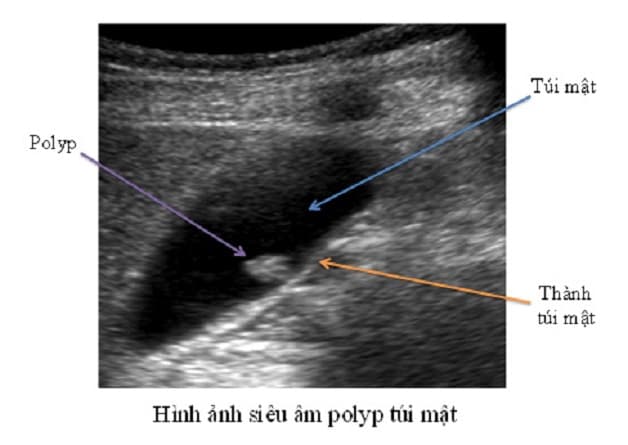

2. Hình ảnh polyp túi mật trên siêu âm

Hình ảnh polyp túi mật hiển thị trên siêu âm phần lớn là hình tăng âm (gần 95%), không có bóng cản (điều này giúp phân biệt với hình ảnh của sỏi túi mật là hình tăng âm, có bóng cản). Hình ảnh tăng âm này bám trên bề mặt niêm mạc của túi mật và không di chuyển khi thay đổi tư thế.

Siêu âm polyp túi mật có tỷ lệ chẩn đoán bệnh chính xác lên đến trên 90% cùng tính thuận tiện, an toàn và chi phí hợp lý. Tuy nhiên siêu âm lại không thể xác định được bản chất của polyp là lành tính hay ác tính, vì thế bác sĩ cần kết hợp thêm các chẩn đoán khác mới có thể đưa ra kết luận cuối cùng.